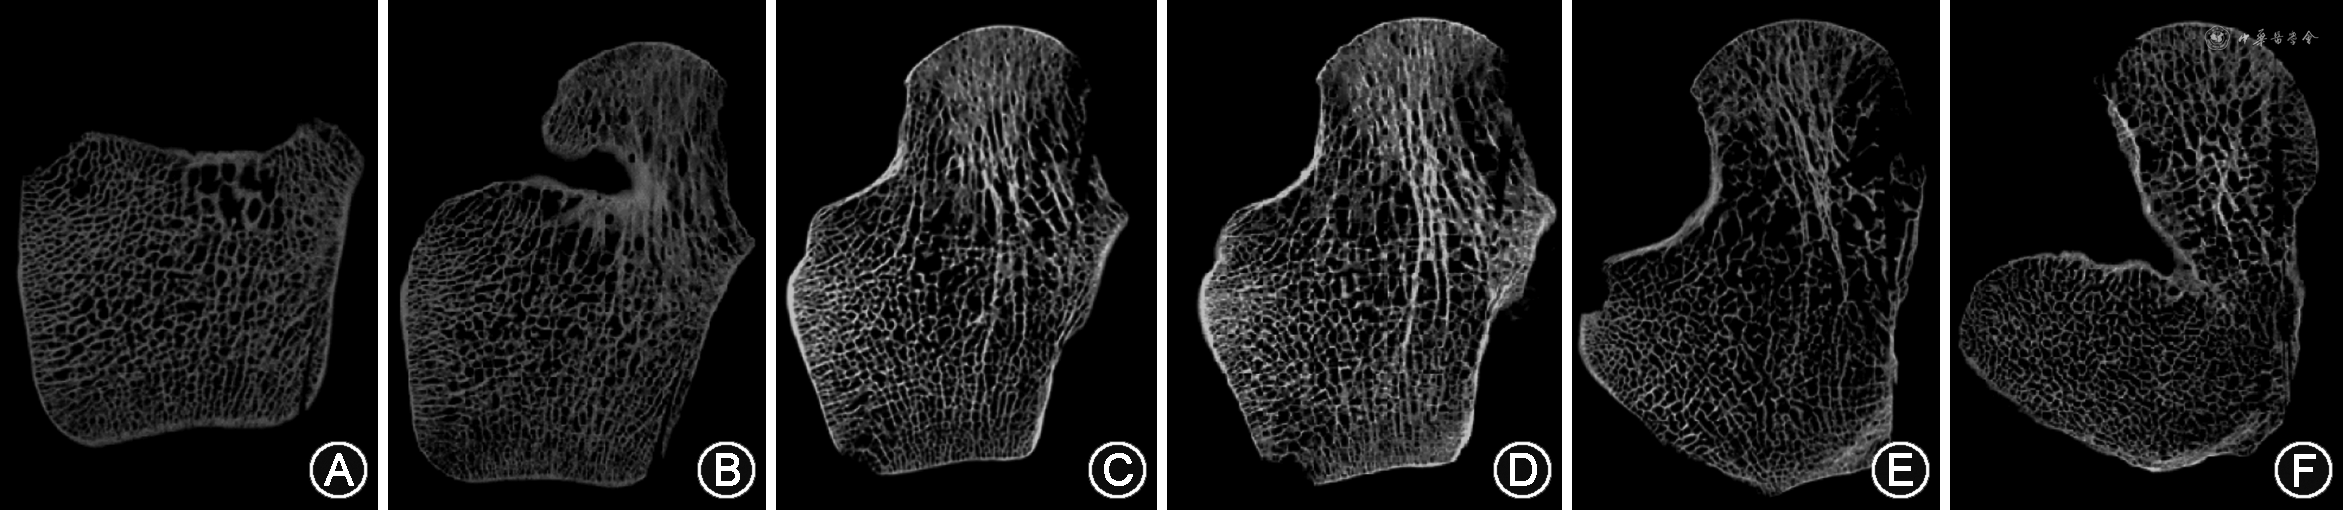

在距骨上部的水平面切片中,距骨切面中部骨小梁主要沿距骨的长轴前后方向排列延伸,同时两侧小梁垂直起始于胫距及腓距关节面,向中部延长轴汇聚,体部小梁排列较颈部较为致密。在颈部区域小梁逐渐变得稀疏且较体部小梁更粗;在头部,小梁方向发生偏转,似板状重叠排列。在水平面切片中部,骨小梁头体密颈疏的特点越发明显,且头体部小梁交织密集,颈部虽较疏松,但颈中部连接头体的小梁明显较距骨颈沿皮质周围的小梁更粗密。在下部,距骨体部小梁呈网格状相互交织,无明显走向;颈部小梁较上中部更为稀疏,使得颈中部小梁粗密程度更为明显,头部小梁与上中部一样保持板状密集,如图3。

从距骨的矢状面切片发现距骨体部小梁呈板状连接,且成片的板状小梁上均有不均匀排布的椭圆形开窗孔。由内向外侧的距骨颈切片显示距骨颈上部小梁较下方靠近跗骨体及跗骨窦部位的小梁更致密,且上方皮质下方出现多层增厚的板状骨结构。经过距骨颈部位的小梁至头颈交界处分为两部分,一部分沿距骨长轴向前小梁平行走行垂直于距舟关节面,为头部小梁的垂直支;另一部分向下平行走行垂直于距跟小关节面,为头部小梁的水平支,如图4。

在距骨头部,小梁交织成网状构成较厚的、平行的半拱形板状小梁结构。这些半拱形板状小梁主要分为垂直支和水平支。垂直支主要占据距骨头部下内侧,位于距跟中、前小关节的上方,水平支则占据头部大部分区域且向距舟关节面垂直走行。两支小梁均向距骨颈部小梁延续并汇合。同时,垂直支与水平支彼此连续,垂直支从距跟前、中关节面垂直向上发出,随后向前转换为水平支的一部分。在距骨颈部,小梁数量逐渐稀疏,大部分小梁并无明显的方向性,仅相互交织呈不规则网状结构,仅有少量中心部小梁由半拱形走行逐渐由背侧向跖侧的垂直走行转变。在距骨体部,小梁相互平行排列并由滑车关节面至距跟关节面走行,如图5。